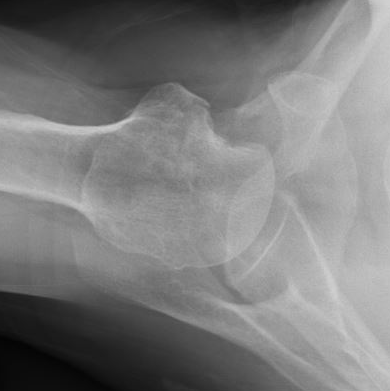

AP Xray

Abnormal overlap of humeral head on glenoid

Light-bulb sign - globular head secondary to internal rotation of the humeral head

Vacant Glenoid Cavity - > 6 mm space between humeral head and anterior rim of glenoid